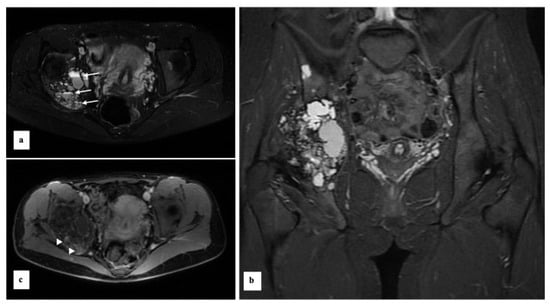

Custom-Made 3D-Printed Prosthesis after Resection of a Voluminous Giant Cell Tumour Recurrence in Pelvis

2. Case Presentation